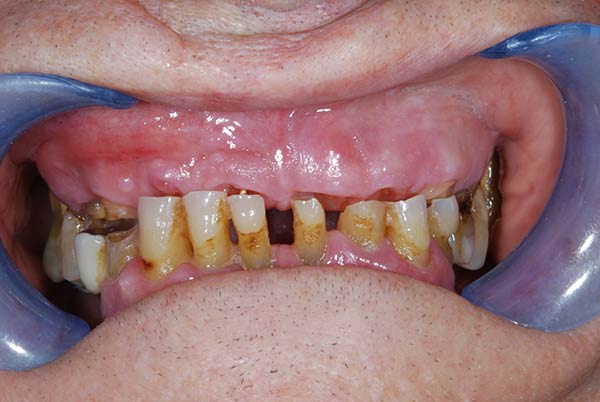

Con protesi fissa superiore e protesi fissa inferiore

I denti irrecuperabili dell'arcata superiore ed inferiore del paziente di anni 65 sono stati sostituiti da 10 impianti, cioè protesi radicolari endo-ossee che sostengono le protesi fisse superiore ed inferiore.